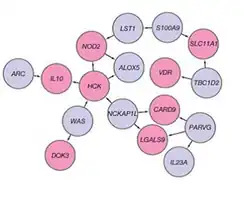

Genome-wide association studies have since added to understanding of the genomics and pathogenesis of the disease. More than 200 single nucleotide polymorphisms (SNPs or "snips") are now known to be associated with susceptibility to IBD.[49] One of the largest genetic studies of IBD was published in 2012.[50] The analysis explained more of the variance in Crohn's disease and ulcerative colitis than previously reported.[48] The results suggested that commensal microbiota are altered in such a way that they act as pathogens in inflammatory bowel diseases. Other studies show that mutations in IBD-associated genes might interfere with the cellular activity and interactions with the microbiome that promote normal immune responses.[51] Many studies identified that microRNAs dysregulation involved in IBD and to promote colorectal cancer.[52] By 2020, single-cell RNA sequencing analysis was launched by a small consortium using IBD patient biopsy material in a search for therapeutic targets.[53]